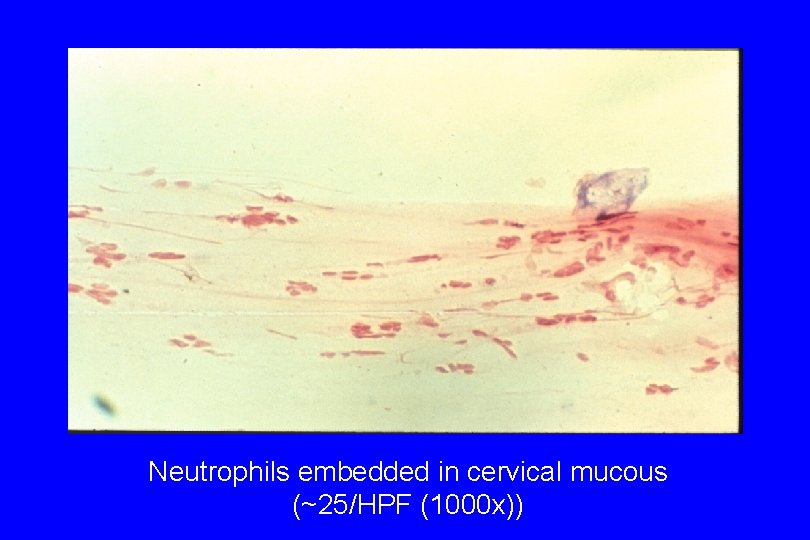

Neutrophils embedded in cervical mucous (~25/HPF (1000 x))

Diagnosis of Cervicitis · · Signs: specific, but insensitive. Include: - easily induced bleeding (“friability”) “Endocervicitis” - mucopurulent discharge: swab test - edematous ectopy - discrete lesions (ulcers): can occur anywhere Increased PMN (“polys; ” >10 -30/HPF) on Gram stain of endocervical secretions: may be sensitive for endocervicitis, but not specific; variable in ectocervicitis

The Swab Test to Detect Mucopurulent Endocervical Discharge